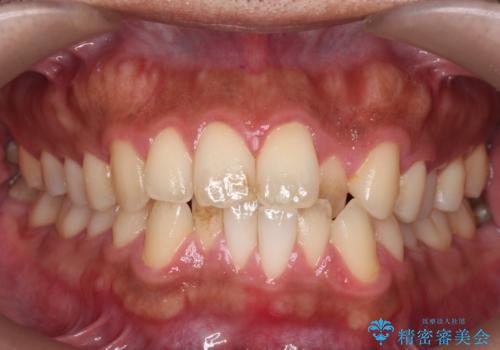

[ 前歯のねじれ・がたつき ] マウスピース矯正

![[ 前歯のねじれ・がたつき ] マウスピース矯正の症例 治療前](https://seimitsushinbi.jp/wp/wp-content/uploads/2024/02/4007c6479f6bce11863dcdd32ed5e39b-500x350.jpg?v=1708502552)

![[ 前歯のねじれ・がたつき ] マウスピース矯正の症例 治療後](https://seimitsushinbi.jp/wp/wp-content/uploads/2024/02/e7a01485e4f4dd0da04705fde4cc34cc-500x350.jpg?v=1708502585)